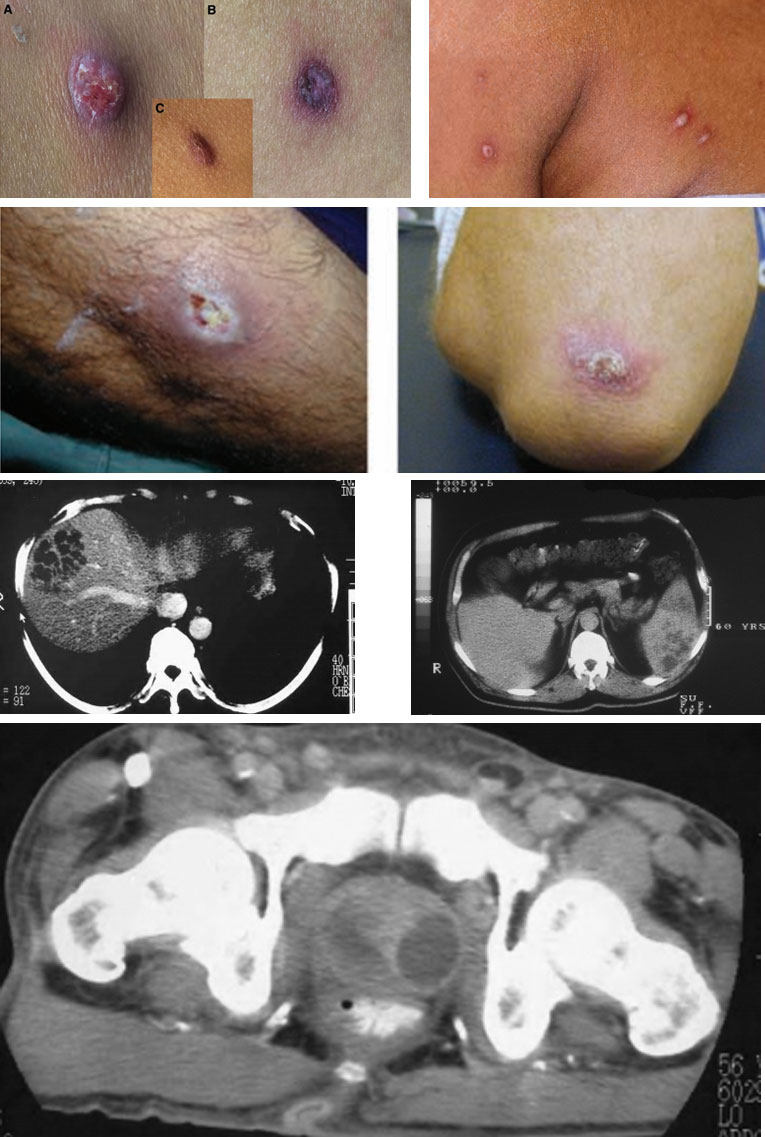

- Tổn thương trên da cơ xương, phần mềm: thường không phải triệu chứng đầu tiên

+ Vết loét hoặc mụn mủ đơn độc hoặc nốt, lâu liền: thể mạn tính, có thể là nguyên phát.

+ Mụn mủ có viền ban đỏ toàn thân: thể cấp tính, xuất hiện thứ phát sau NKH.

+ Abscess phần mềm dưới da, viêm mô tế bào.

+ Viêm khớp nhiễm khuẩn và viêm tuỷ xương: có tính chất mạn tính.